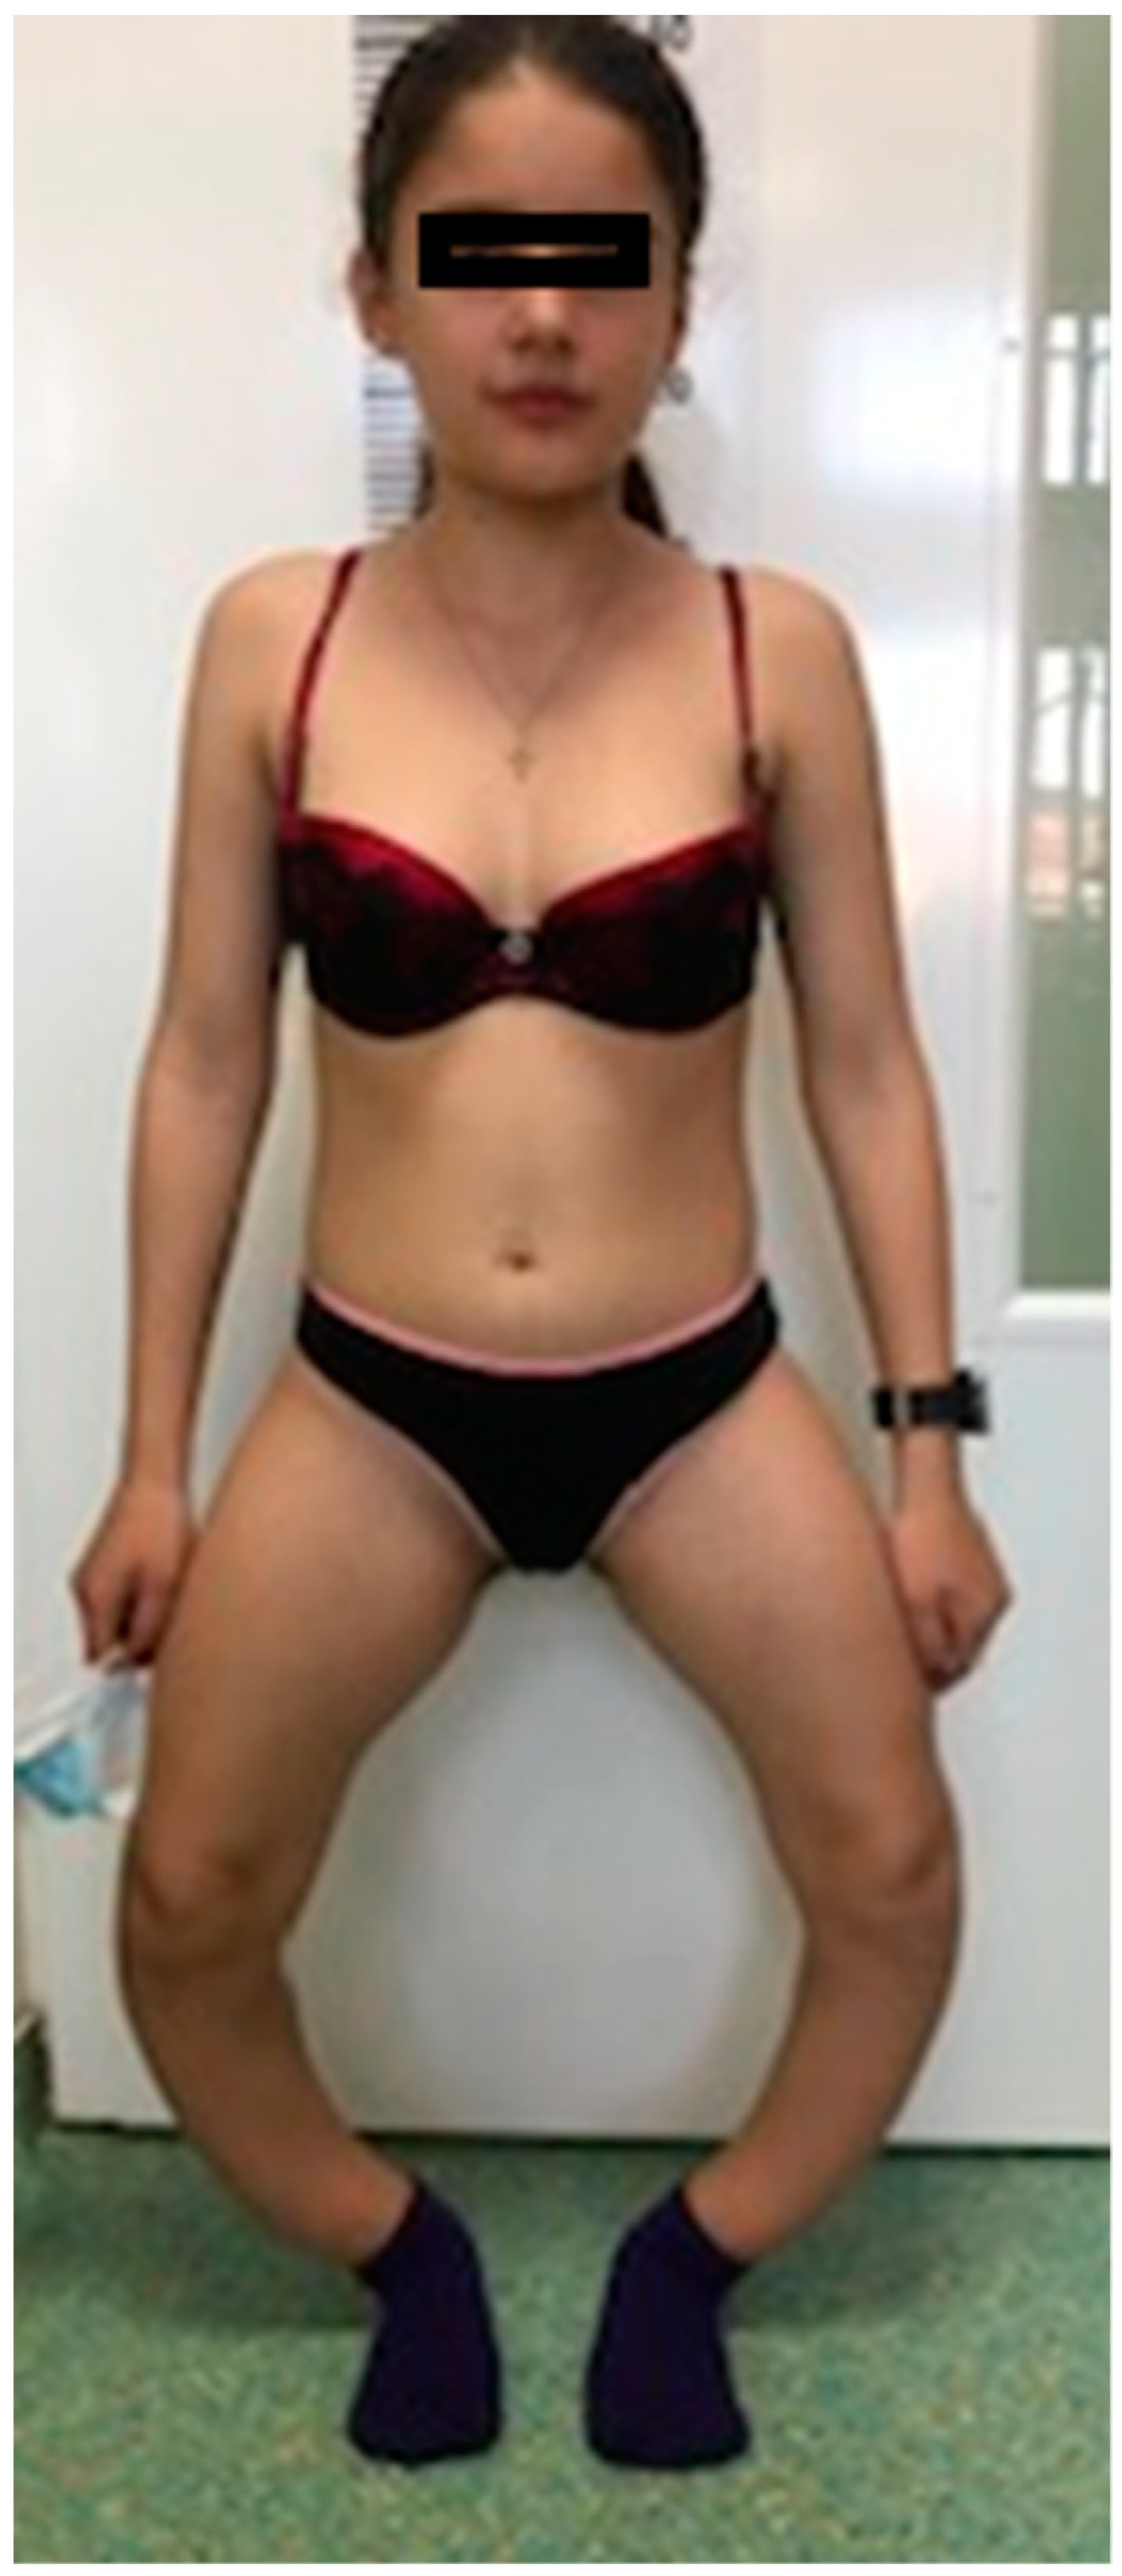

3.1. Morphological Evaluation of the Patients

| Musculoskeletal abnormalities | thickened wrists and ankles, severe bilateral bowing of lower limbs (genu varum) | thickened wrists and ankles, genu valgum deformity (knees touching each other while the ankles remain spaced apart) |

| Walk | waddling gait | impaired |

| Walking fatigue | ++++++ | +++ |